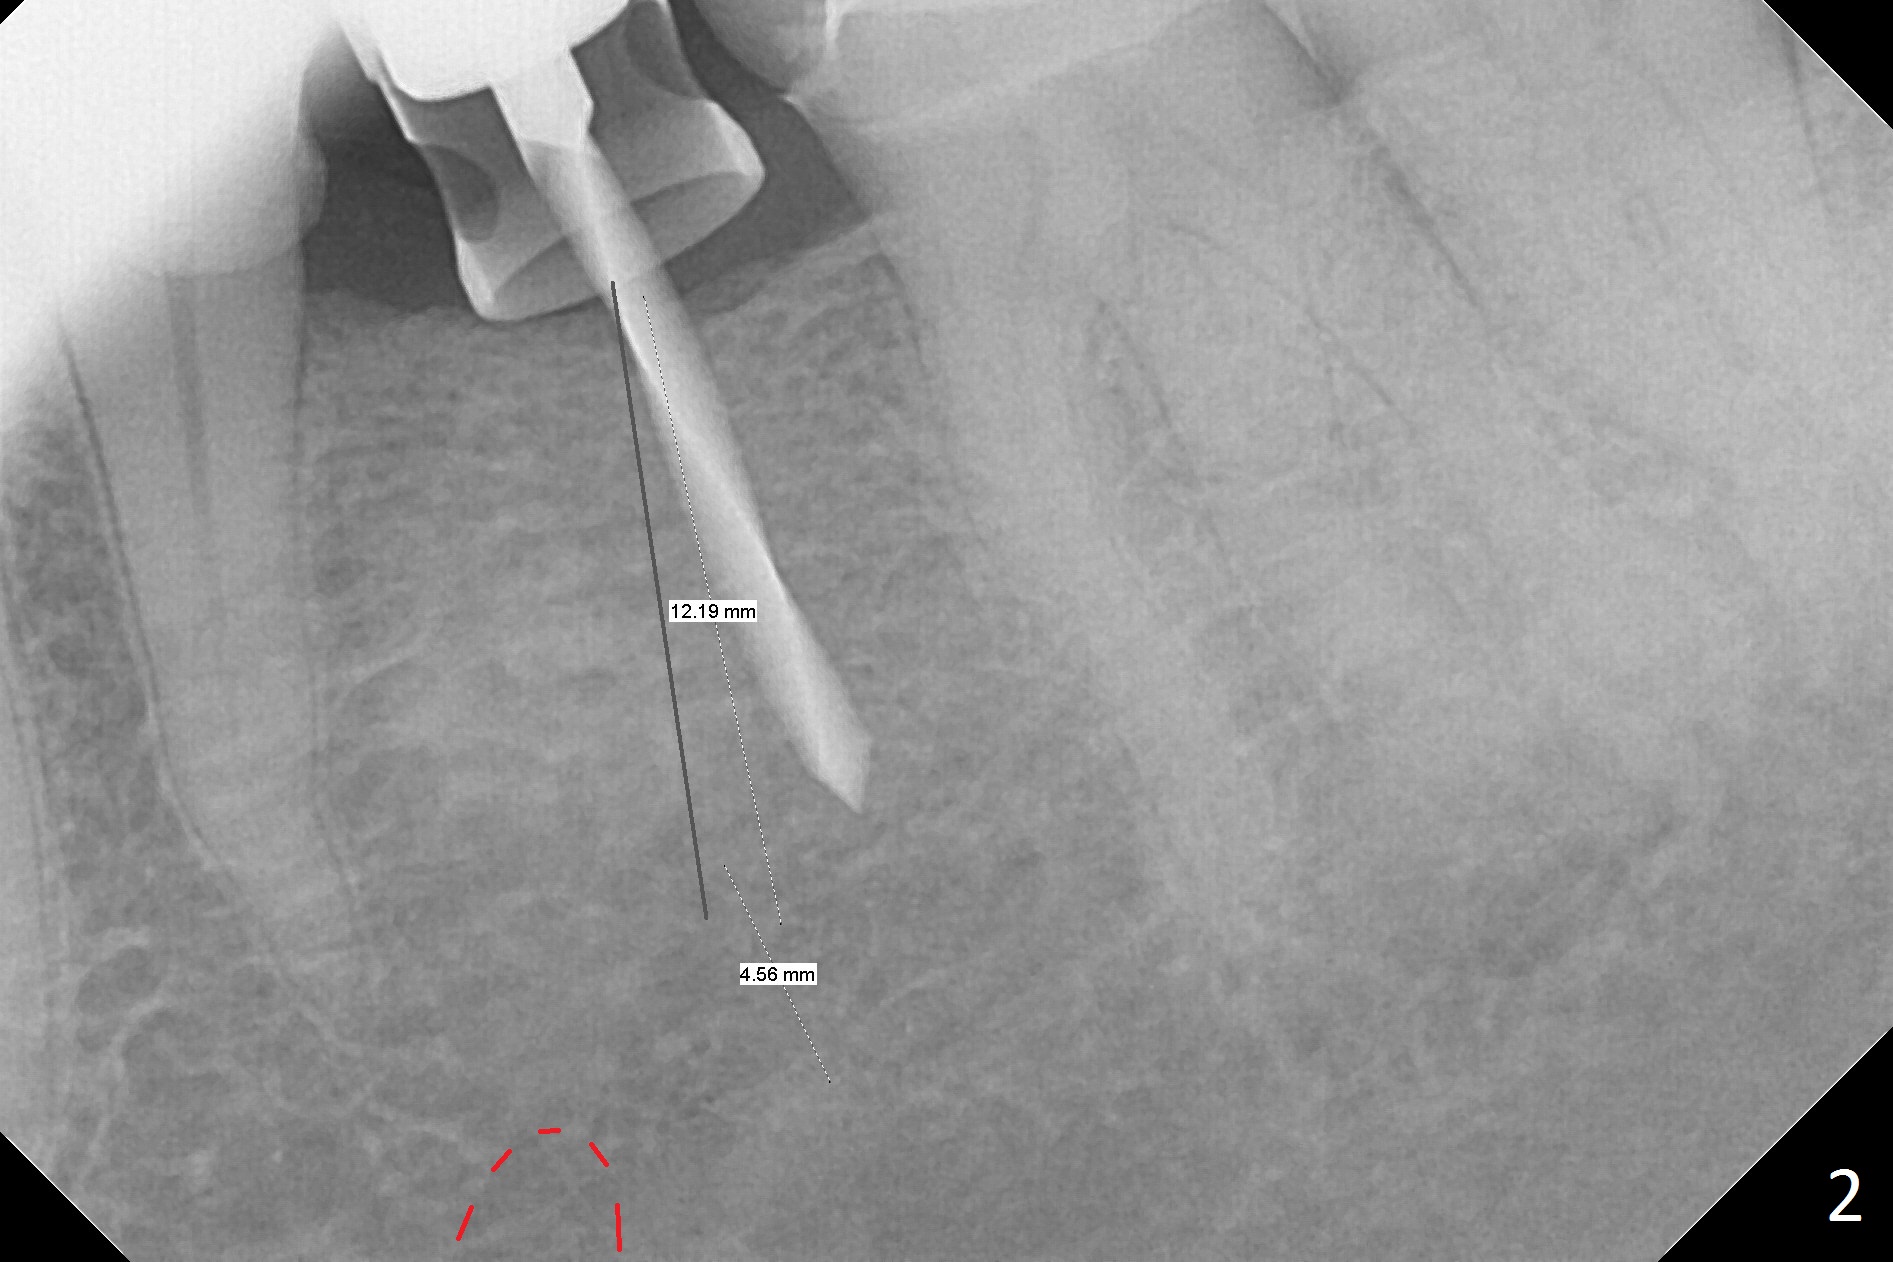

Initial osteotomy with 1.6 mm drill for 11 mm seems to be distal (Fig.1).  The trajectory should be changed as shown by the black line in Fig.2; the drawback would be close to the Mental Loop (red line).  Fortunately the trajectory is changed, but not so much as to be close the Loop when a 4x11 mm dummy implant is placed (Fig.3).   When a 4x13 mm IBS is placed with 46 Ncm, there is clearance from the Loop (Fig.4-6).  In fact there is no postop paresthesia.  The main point is no block anesthesia.  Infiltration anesthesia is administered with 34 mg Xylocaine with 17 mcg Epinephrine.  The patient experiences dull pain when the implant is placed (Fig.4-6).  After further anesthesia with 68 mg Septocaine, 17 mcg Epinephrine, the implant is torqued for a few turns (still with some discomfort).  Finally autogenous bone with Osteogen is placed around the implant following placement of a 4.5x4(2) mm abutment.  To reduce anxiety, a shorter implant should have been used. The patient complains of cold sensitivity in the lower left quadrant 4 months postop (Fig.7): the implant apparently close to the Mental Loop.  Without an immediate provisional, the gingiva around the abutment is healthy.